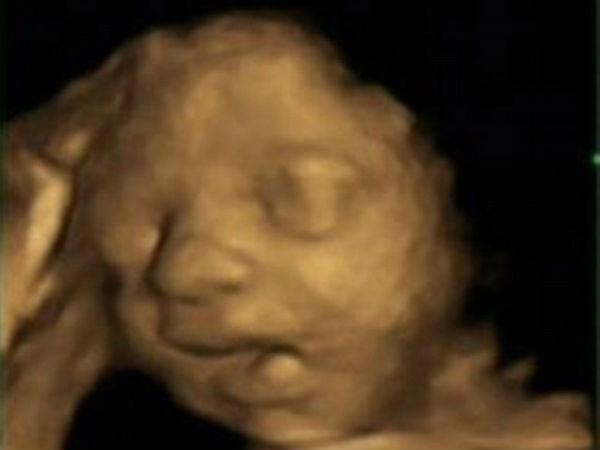

માના ગર્ભમાં આ રીતે વિકસે છે બાળક

આ છેલ્લી તસવીરમાં બાળકનું મુખ સંપૂર્ણ રીતે વિકસિત થઇ ગયેલું નજરે પડે છે.